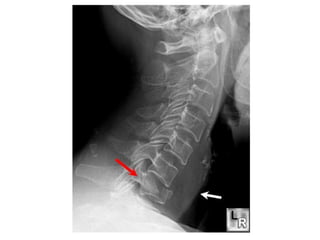

• Investigations

– Confirmatory

• Xrays

• CT

• MRI

• Myelography